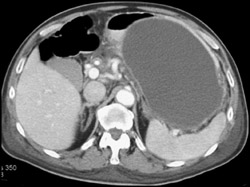

Ampullary Mass C/w Adenocarcinoma